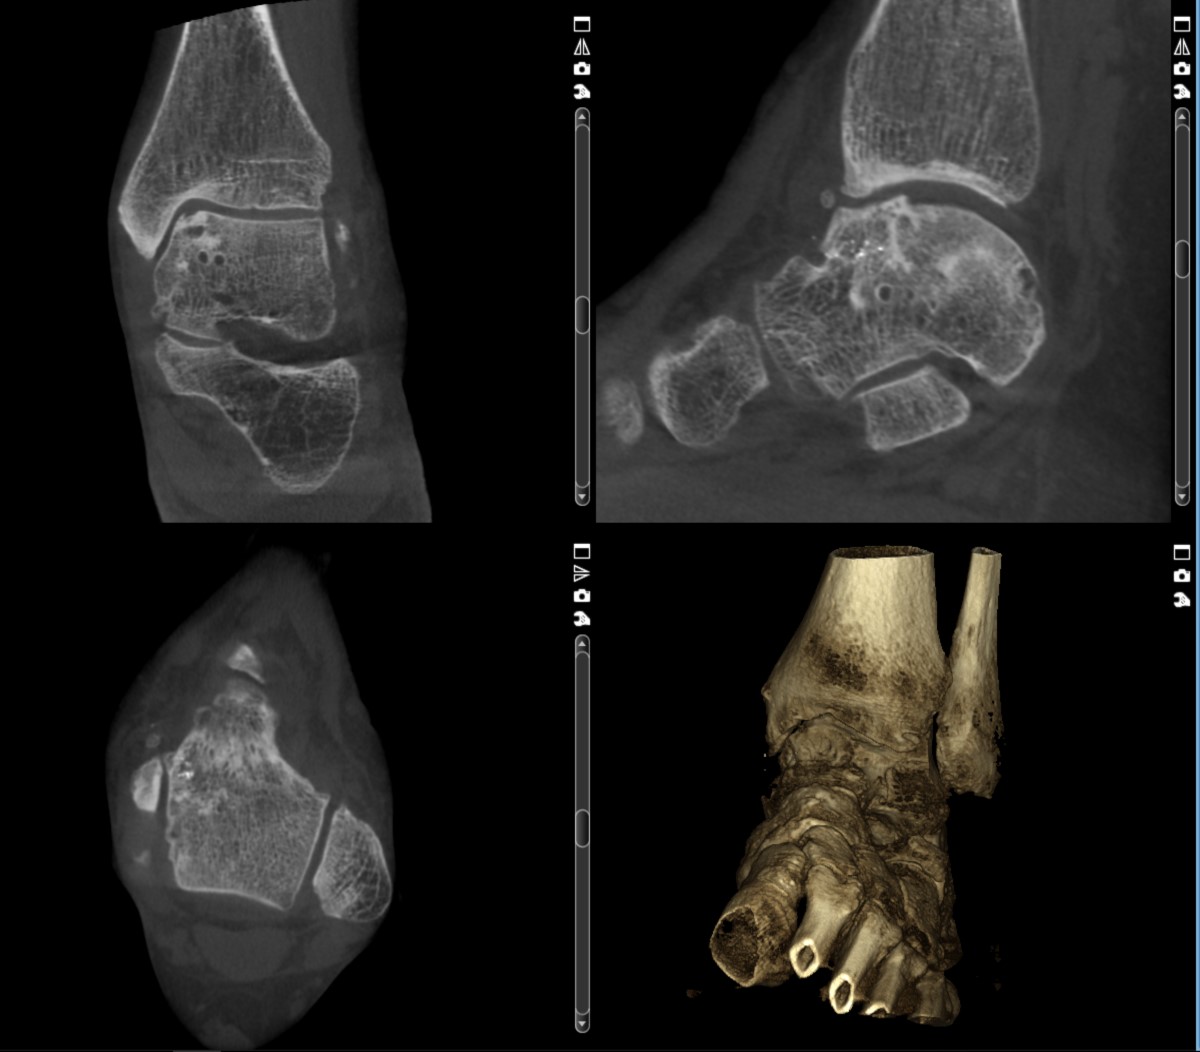

- Genaue Lokalisation freier Gelenkkörper,

- Erkennung der Früharthritis durch exakte Darstellung der Gelenkflächen,